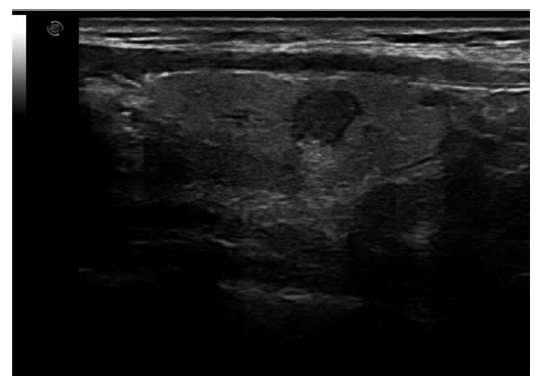

XU Shangyan, JIA Xiaohong, NI Xiaofeng, ZHAN Weiwei. Interobserver variability in sonographic evaluation of thyroid nodules with ACR-TIRADS and RJ-TIRADS[J]. Journal of Diagnostics Concepts & Practice, 2019, 18(2): 149-154.